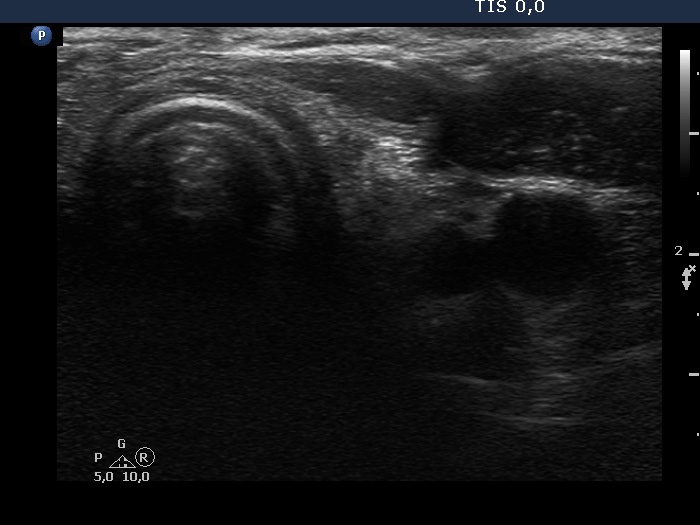

Eleven years after surgery (second and third rows of images):

Clinical data: The patient came to a follow-up. He told us that he decided not to visit the surgeon because the mass did not cause any complaints. He didn't remember exactly, but a few years ago he couldn't feel the knot at all, it had slowly disappeared on its own over the years.

Palpation: no abnormality.

Laboratory tests: TSH 3.56 mIU/L on daily 75 microgram levothyroxine.

Ultrasonography. The right lobe remained unchanged. Compared with the previous finding, a much smaller, inhomogeneous mass was found according to the left lobe. A few centimeters above and ventral to the left lobe, a cystic lesion was found within the strap muscle and close to this, an amorphous hyperechoic fragment was also present (see video).